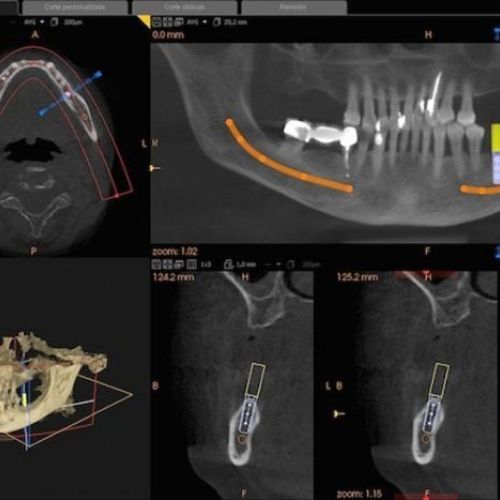

En Imagen Diagnóstica Dental Dr. Mayor te ofrecemos una de las últimas técnicas del mercado para realizar mediciones precisas de la calidad ósea del maxilar o la mandíbula: el DentaScan en Madrid. Este estudio tomográfico resulta especialmente útil a la hora de realizar implantes con éxito, ya que permite conocer la estructura ósea de la pieza y de esta forma fijar la posición exacta en la que se va a colocar el implante en el hueso. Además, este tipo de TAC dental permite conocer el estado de la raíz del diente.

El DentaScan fue el primer programa específico que estudió las estructuras anatómicas dentarias. Se trata de un programa computacional para escáner que permite captar imágenes de alta resolución de maxilar y mandíbula, algo que sirve para realizar reconstrucciones panorámicas y transversales a partir de cortes en el plano axial.

Las imágenes se entregan en escala natural, 1:1. Son imágenes de gran claridad y sin superposición de estructuras o distorsiones como en la radiología convencional, lo que permite una reproducción exacta y medida de las estructuras anatómicas en los tres planos del espacio.

Ambas técnicas utilizan las Unidades Hounsfield (H.U.) para valorar la calidad ósea del paciente por lo que el DentaScan resulta compatible compatible con todos los programas de cirugía guiada del mercado.

Entre los beneficios del DentaScan en Madrid está la utilización de un nuevo software capaz de realizar cortes transversales, que junto a los otros beneficios del tratamiento permite al profesional obtener un diagnóstico específico y de esta forma garantizar al paciente una buena planificación de su tratamiento, lo que se traduce en mayor rapidez y eficacia.